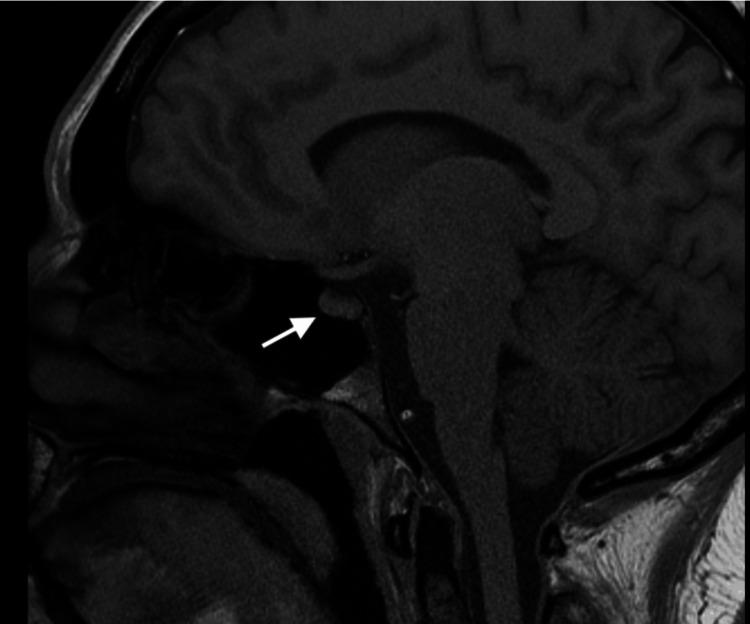

Autoimmune hypophysitis (AH) is an uncommon condition where there is inflammation of the pituitary gland which leads to hormonal imbalances. It is often associated with autoimmune diseases; however, a case is yet to be reported with an association of AH with seronegative rheumatoid arthritis (RA). We present a case of a 45-year-old female who complained of polyuria/polydipsia and rapid weight gain. An MRI of the head revealed enlargement of the pituitary gland, concerning for AH. Although she was initially treated for diabetes insipidus, she began reporting new complaints of joint pains and morning stiffness. She was clinically diagnosed with seronegative RA and improved with a trial of hydroxychloroquine. A repeat MRI showed improvement in the abnormal pituitary findings, and the patient was closely monitored with a multidisciplinary approach. Diagnosing and managing patients with AH are topics that are still being explored and researched as it is a relatively rare pathology. Consequently, we found the need to discuss the relationship of AH with seronegative RA and delve into the various diagnostic and treatment approaches.

自身免疫性垂体炎(AH)是一种罕见的疾病,其特征为垂体发生炎症,进而导致激素失衡。它常与自身免疫性疾病相关;然而,AH与血清阴性类风湿关节炎(RA)相关的病例尚未见报道。我们报告一例45岁女性患者,她主诉多尿/烦渴及体重快速增加。头部MRI显示垂体增大,怀疑为AH。尽管她最初接受了尿崩症的治疗,但她开始报告新的关节疼痛和晨僵症状。她临床诊断为血清阴性RA,试用羟氯喹后病情改善。复查MRI显示垂体异常表现有所改善,患者采用多学科方法进行密切监测。由于AH是一种相对罕见的病理情况,对AH患者的诊断和管理仍是正在探索和研究的课题。因此,我们认为有必要讨论AH与血清阴性RA的关系,并深入探讨各种诊断和治疗方法。